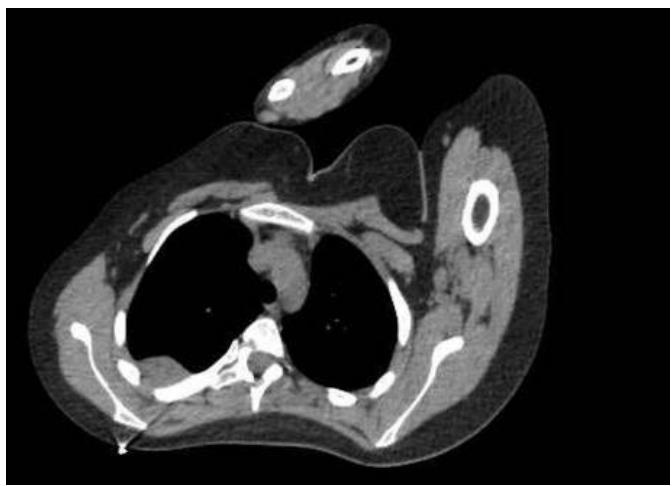

Introduction: Understanding that cancer is a pathology that is challenging to detect, treat, and comprehend is what makes the study of cancer so important. The goal of this case study is to show how a 20-year-old woman was affected by a variety of factors and symptoms that, when combined, raised suspicion of Ewing’s sarcoma, the second most common primary tumor in children and young adults. Ewing’s sarcoma has the characteristics of being an aggressive malignancy originating in the bones.